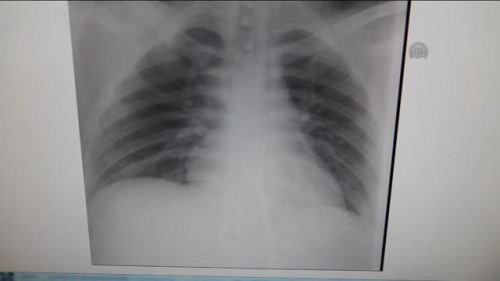

GÖRÜNTÜ DÖKÜMÜ : Midedeki çatalın röntgeni Mideden çıkan çatal Hastanenin Genel Cerrahi Anabilim Dalı Öğretim Üyesi Prof. Dr. Mehmet Erikoğlu ile röportaj Midesinden "çatal" çıkarıldı Konya'da 20 yaşındaki bir gencin yuttuğu 15 santimetrelik metal çatal operasyonla alındı Necmettin Erbakan Üniversitesi Öğretim Üyesi Prof. Dr. Erikoğlu: "Çatal tersten yutulduğu için vücuda bir zararı olmamış. Bugüne kadar çatal yutmasıyla ilk kez karşılaştık" METİN BOLAT - Konya'da bir gencin yuttuğu 15 santimetrelik metal çatal, midesinden ameliyatla çıkarıldı. Çeşitli sağlık problemleri olduğu belirtilen 20 yaşındaki O.A'nın çatal yuttuğunu fark eden ailesi, oğullarını Necmettin Erbakan Üniversitesi (NEÜ) Meram Tıp Fakültesi Hastanesine götürdü. Çekilen röntgen filmlerinde, çatalın midede olduğu görüldü. O.A'nın midesinden 15 santimetrelik metal çatal, başarılı operasyonla çıkarıldı. O.A, taburcu edildi. "Çatal yutmasıyla ilk kez karşılaştık" Hastanenin Genel Cerrahi Anabilim Dalı Öğretim Üyesi Prof. Dr. Mehmet Erikoğlu, AA muhabirine yaptığı açıklamada, O.A'nın acil servise başvurarak, çatal yuttuğunu söylediğini anlattı. Kontrollerde çatalın yemek borusunun sonuna kadar inip midede kaldığını gördüklerini aktaran Erikoğlu, büyük olması nedeniyle çatalı operasyonla mideden küçük kesiyle çıkardıklarını ifade etti. Küçük bazı yabancı cisimlerin mideden atılabildiğini anlatan Erikoğlu, "Yabancı cisim düz yutulmuş olsaydı, ciddi sıkıntılar doğabilirdi. Çatal tersten yutulduğu için vücuda bir zararı olmamış. Bugüne kadar çatal yutmasıyla ilk kez karşılaştık." diye konuştu. Erikoğlu, yabancı cisimlerin vücuda vereceği zararın büyük olabileceğini, ailelerin özellikle bu konularda dikkat etmesi gerektiği uyarısında bulundu.